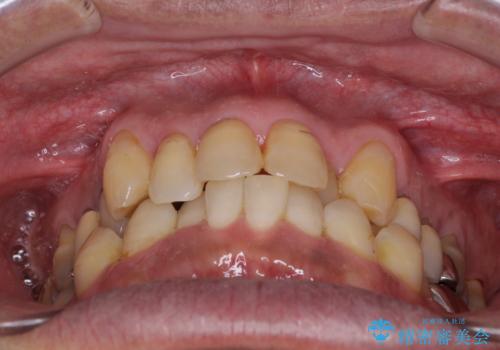

歯列不正と歯周病 総合歯科治療による全顎治療

- 前歯がのデコボコや、奥歯に咬んだときに痛みがあるとのことで来院された患者様です。

全体的に問題が多く、全てをしっかりと治療したいとのことでした。

全体的に中等度の歯周病と診断されたため、歯周外科処置やインプラントによる咬合回復から進めて行き、矯正治療による歯列改善を行った後にオールセラミッククラウンにて補綴することとしました。

歯槽骨の再生治療を行ったため、外科処置後の静置期間がながくなり、4年弱の治療期間となりました。

初診来院時には矯正治療を行うことは想像していなかったようで、治療後には咬みやすさだけでなく、前歯が大変審美的に仕上がり、患者様には大変満足していただきました。